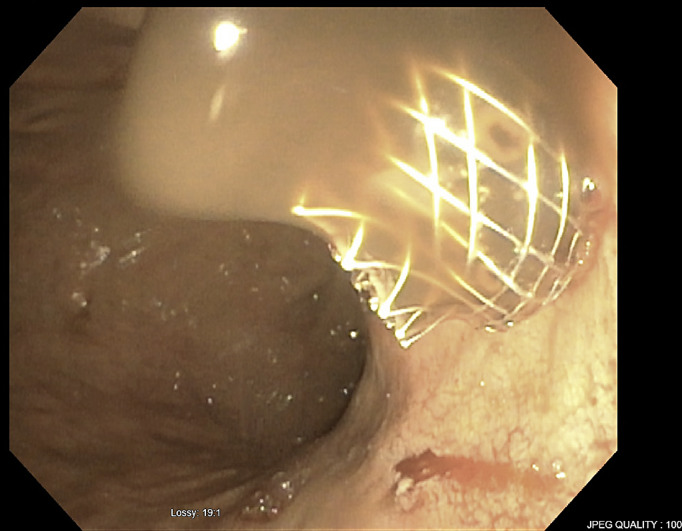

Introduction: Hepatic cysts, commonly discovered incidentally, can become symptomatic due to complications like infection, rupture, or mass effect. Traditional management options include percutaneous drainage, open surgical or laparoscopic deroofing, and liver resection. We present a case series of 3 patients with complex fluid collections in the liver managed by endoscopic ultrasound (EUS)-guided drainage using lumen-apposing metal stent (LAMS) placement. While reports exist from other countries, our study contributes a series of cases from the USA.

Case presentation: Three patients, average age 75 years (two men, one woman), underwent EUS-guided drainage using LAMS for an infected liver cyst, infected liver hematoma within a hepatocellular carcinoma lesion, and a symptomatic simple liver cyst, respectively. All the hepatic fluid collections were in the left hepatic lobe and had an average diameter of 11 centimeters (cm). Only the female patient with a symptomatic cyst had prior percutaneous drainage. Successful LAMS placement was achieved in all cases. Clinical success, defined as cyst resolution or significant size reduction, was observed in all patients. The superinfected liver cyst showed complete resolution, yet the stent remained in place as the patient transitioned to hospice and subsequently passed away. In the case of the superinfected liver hematoma, the stent was removed after 2 months. No recurrence was observed in follow-up imaging 8 months later, and the patient passed away. The symptomatic simple liver cyst patient had the stent removed 15 months later, with no recurrence in imaging 11 months of post-stent removal.

Conclusion: EUS-guided LAMS placement emerges as a less invasive and viable option for treating symptomatic and/or infected hepatic fluid collections compared to surgery or percutaneous drainage. While it may be a preferable choice in institutions with the requisite expertise, further studies are essential to establish its definitive role as a first-line intervention.